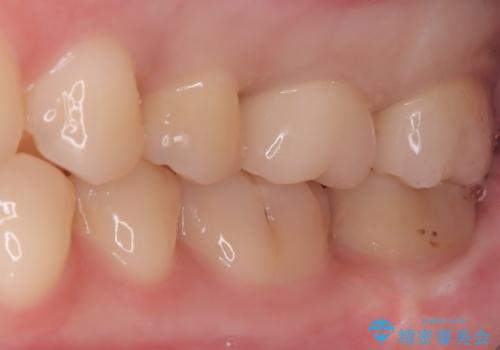

セラミックによる修復: 最終的な被せ物(または詰め物)にはセラミックを使用しました。高い適合性により、二次的な虫歯のリスクを抑えつつ、天然歯のような自然な咬み心地と美しさを再現しました。